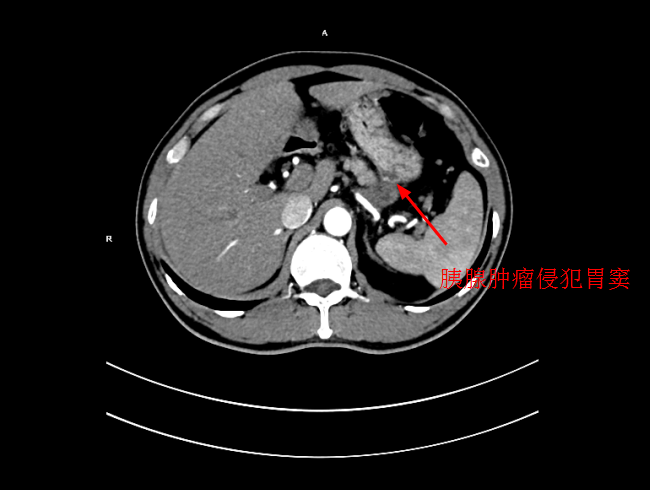

患者陳某,男,49歲,2個月前出現中上腹隐痛不适,伴有腰背部疼痛,在當地醫院就診,考慮爲胃窦炎、胃窦黃斑瘤,治療後症狀未見好轉,遂來我院就診。經過檢查後,确診爲局部晚期胰腺癌,大小爲5*3cm,癌細胞已侵犯胃窦。考慮到傳統化療方式,藥物經身體多重代謝後,到達胰腺的濃度低,達不到很好殺滅腫瘤組織的效果,且對正常組織具有一定的毒副作用。爲此李旭丹主任決定給予采用DSA下介入灌注化療,得到患者及其家屬的支持。

4月30日下午,李旭丹主任與胡志華主任上台實施介入化療術,在DSA造影下,清晰可見胰腺腫瘤的供血動脈,專家們将微導管經股動脈穿刺送達瘤體的供血動脈,成功将化療藥物灌注至瘤體,順利完成手術。術後,患者症狀明顯好轉,并于5月4日順利出院。